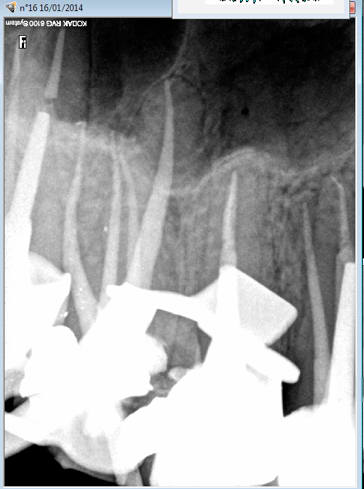

Du coup jean mich a évité de passer par la case cerec pour traiter la 16. -)

Capture d e cran 2016 04 26 21.25 - Eugenol